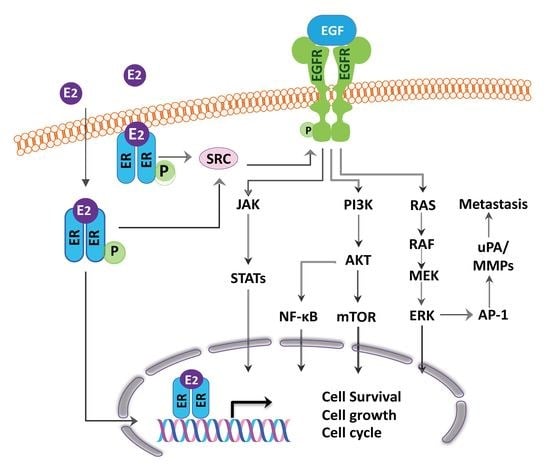

4. ER as Targets for Lung Cancer Therapy and Relationship with EGFR